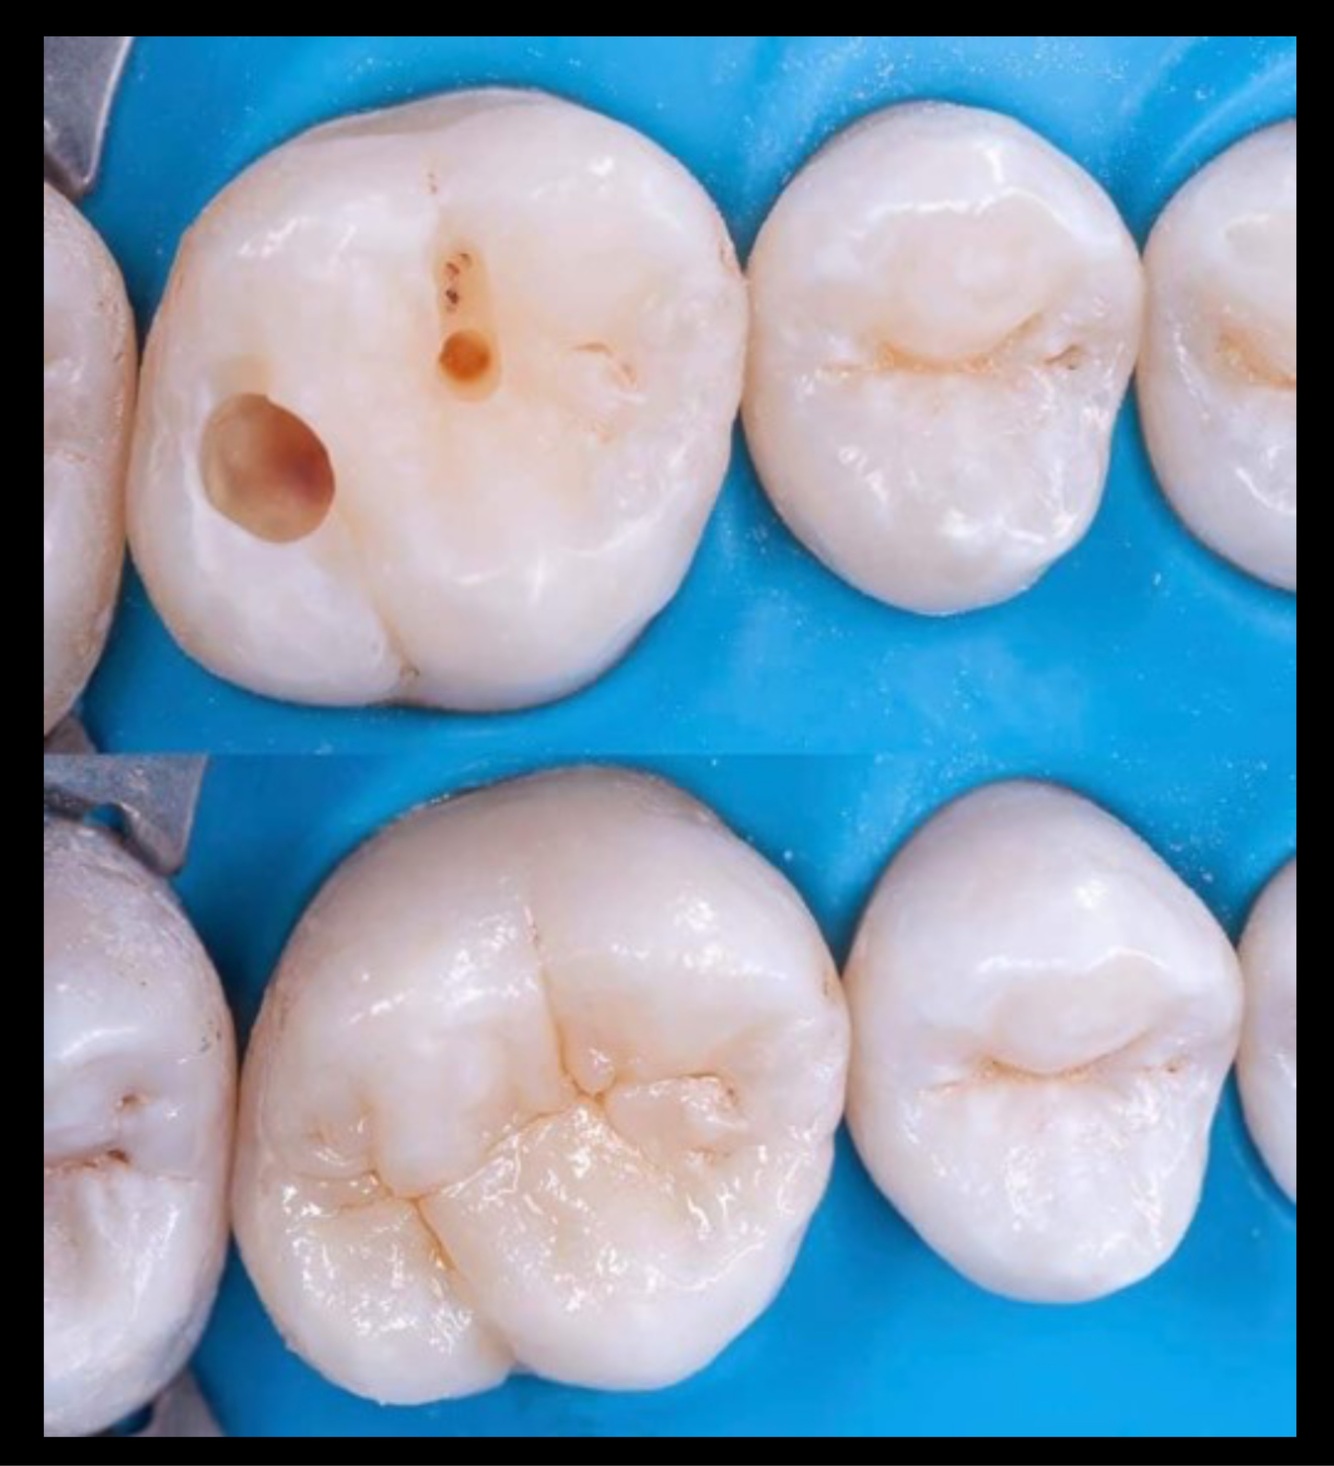

11

Q

Which premolar has the mesial marginal ridge lower (more cervical) than the distal marginal ridge?

A

12

This tooth is:

44

45

24

25

13

34

15